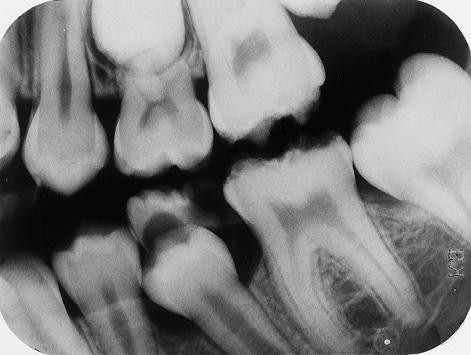

3. In the X ray bellow for which jaw periodontal bone loss is evident?